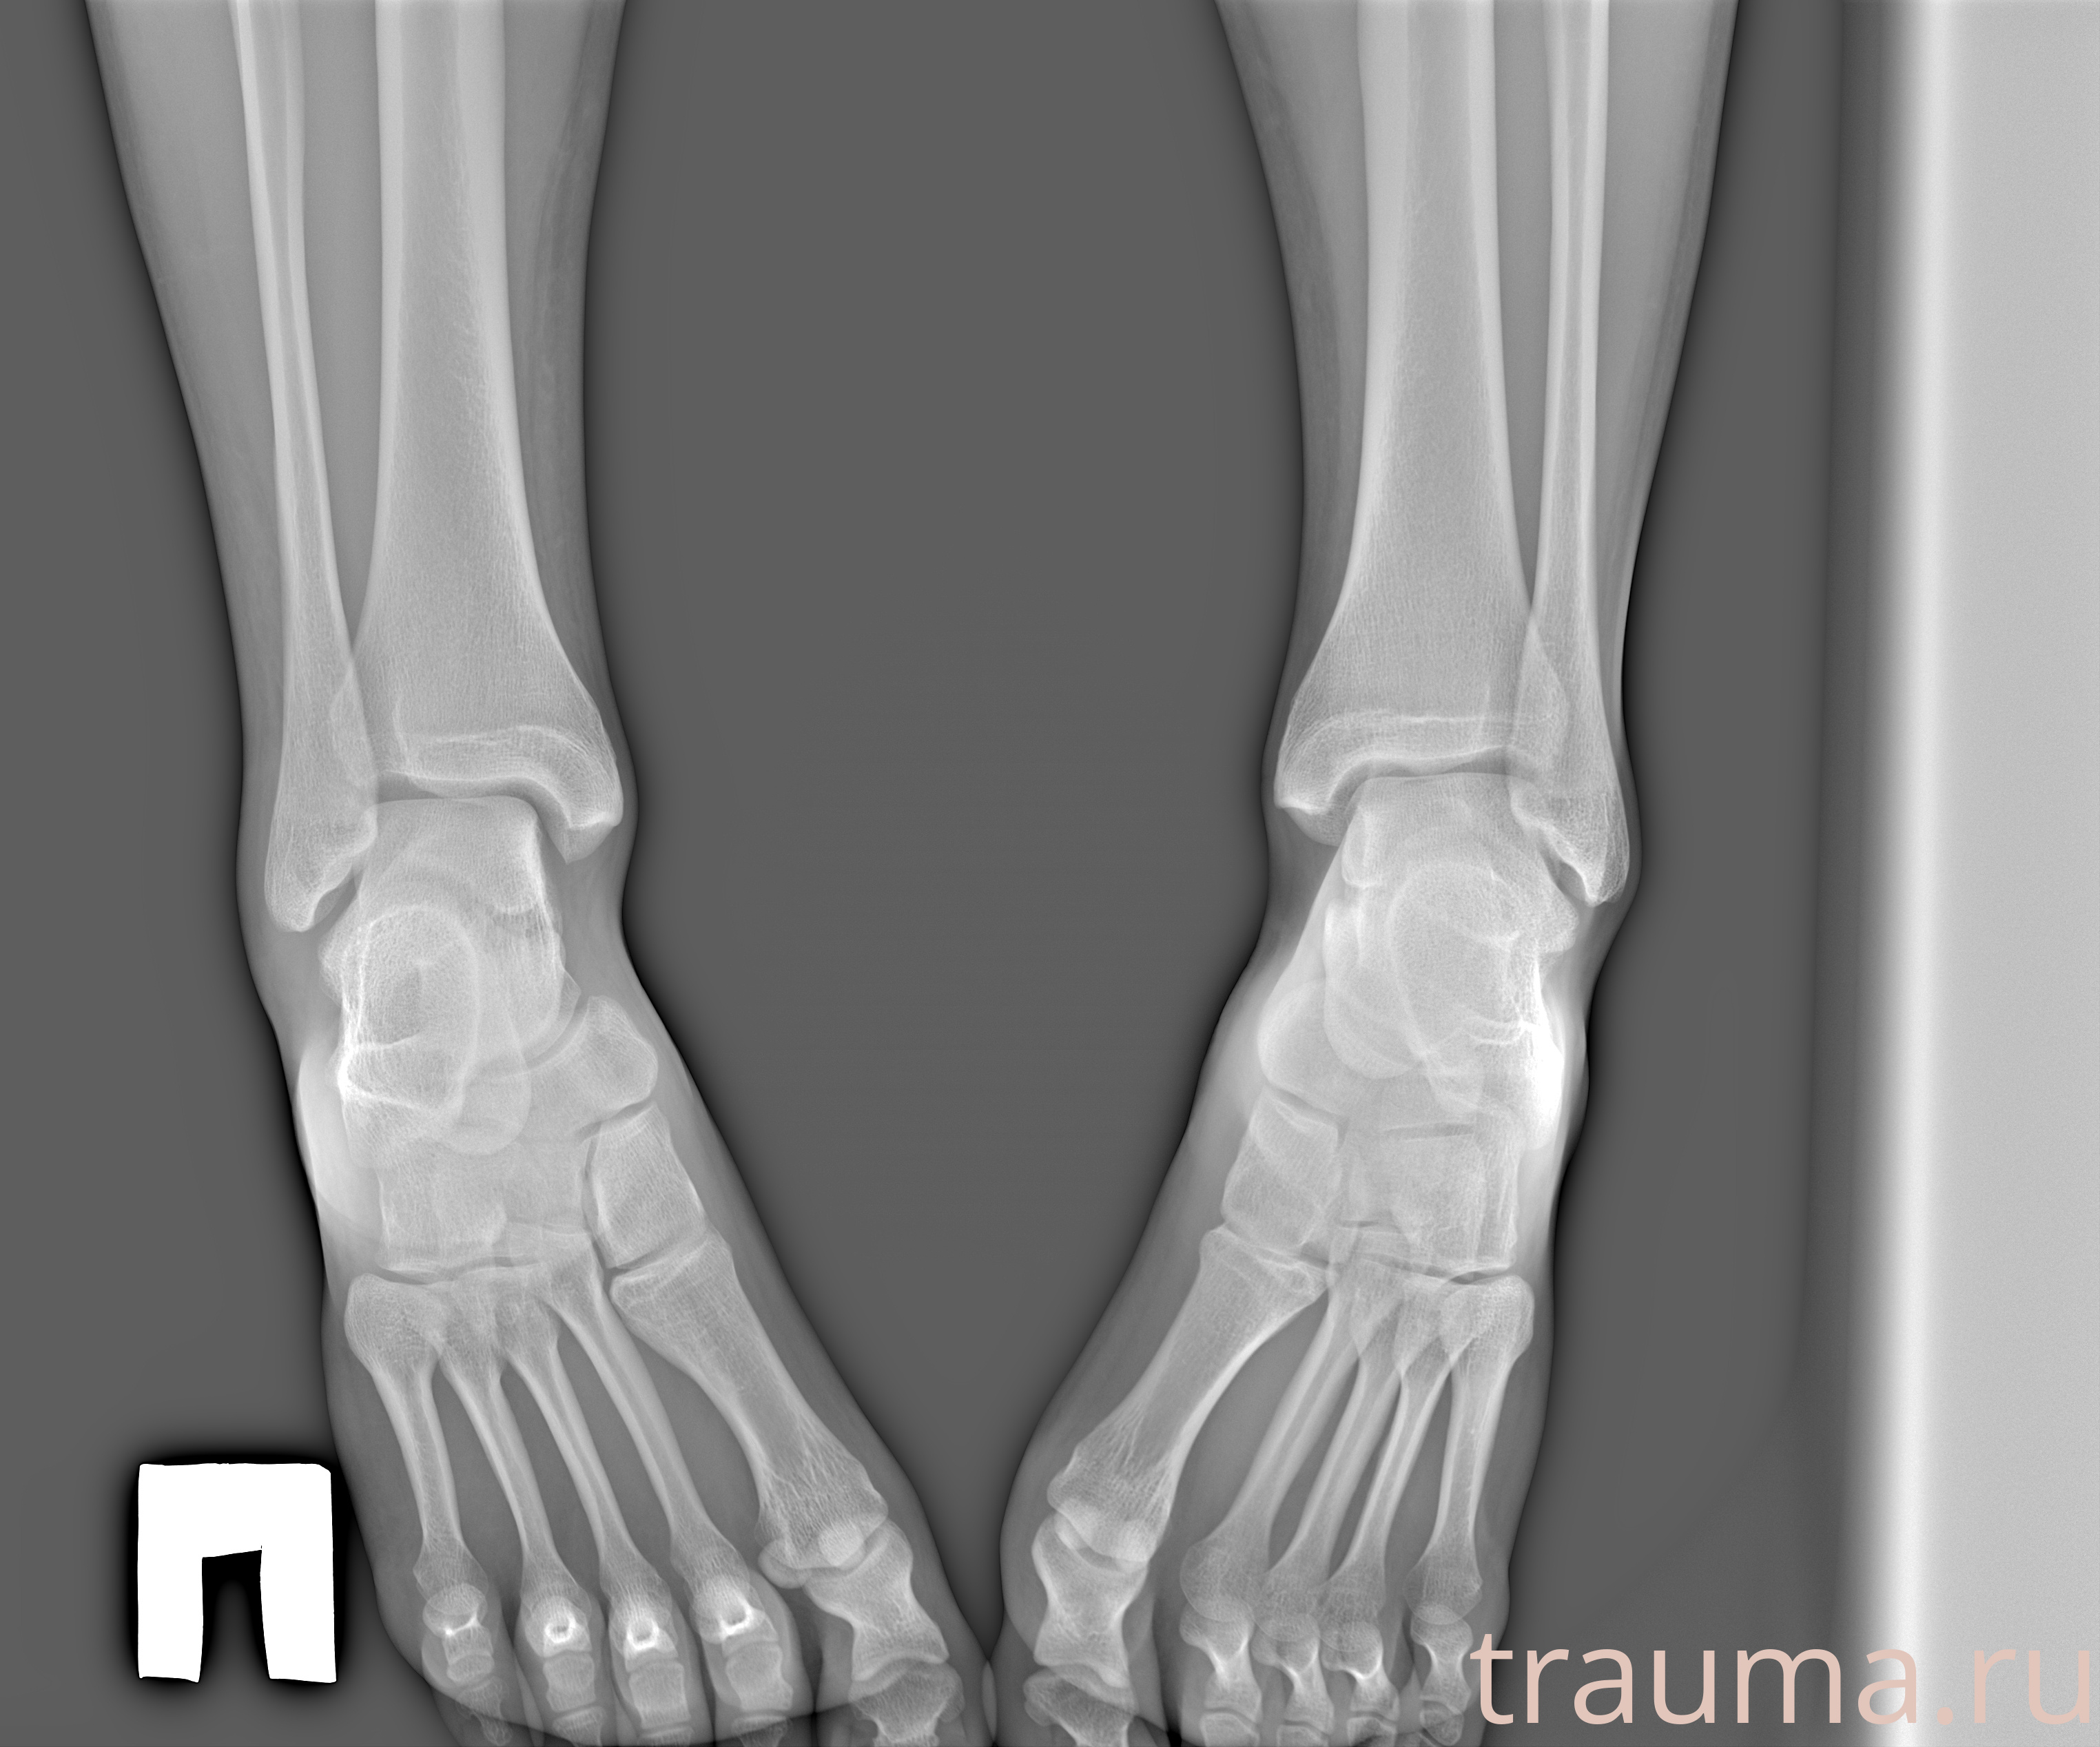

Рентгенограммы

Рентген на дому: по вашему адресу приезжает врач-рентгенолог, травматолог-ортопед с мобильным рентгеновским аппаратом, проводит диагностику травмы или заболевания, делает необходимые рентгенограммы, дает рекомендации по дальнейшему лечению. Получить качественные снимки в домашних условиях возможно благодаря уникальной методике, разработанной МосРентген Центром для института  Склифосовского